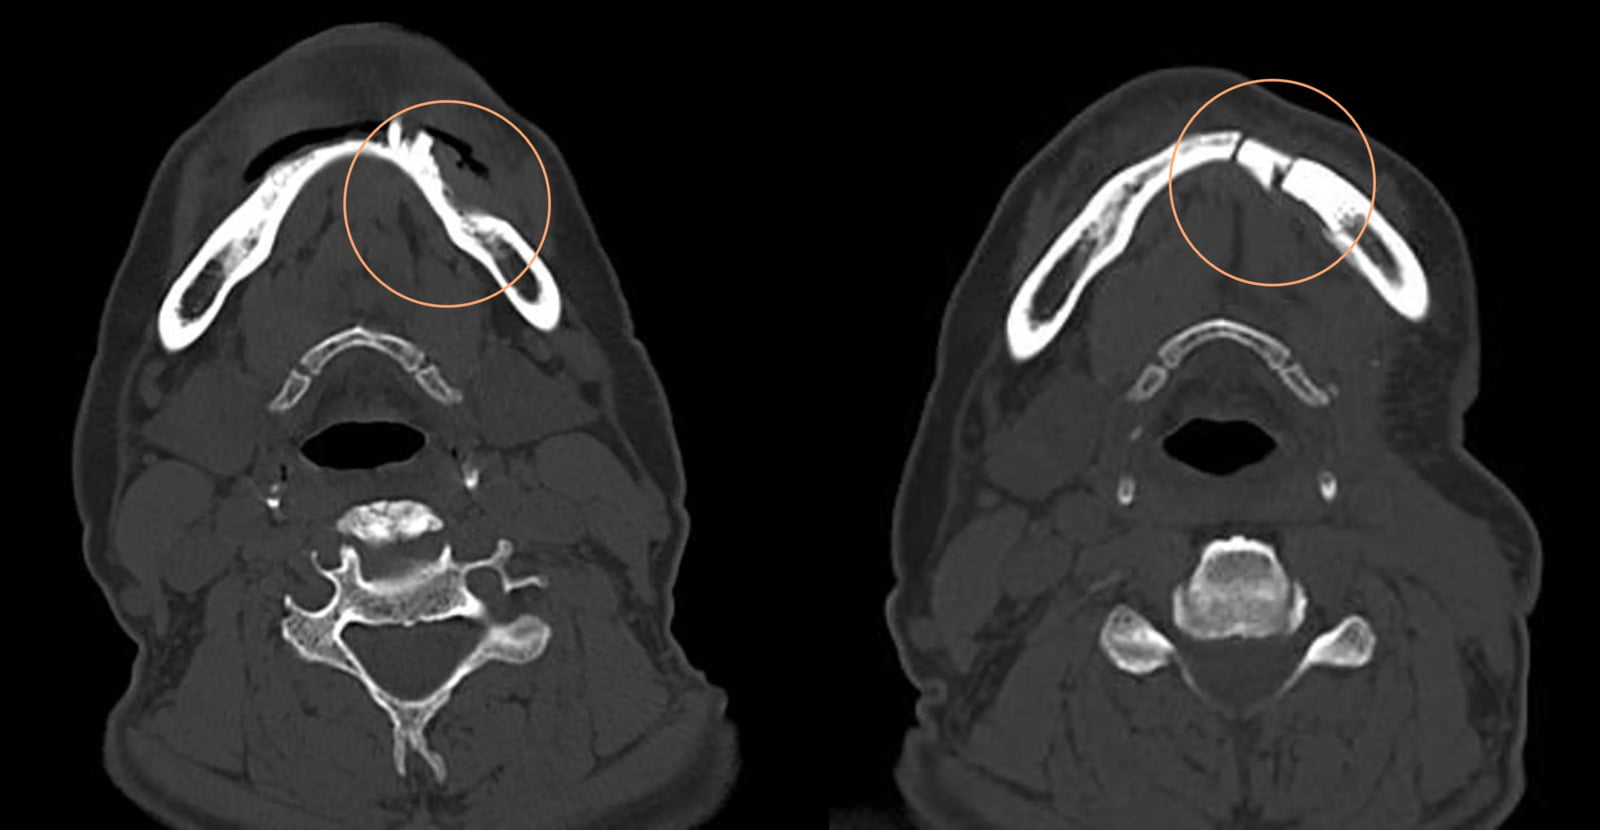

Note: The above clinical studies on reconstruction and bone regeneration of critical-sized bone defects particularly around those defects in the 1–3.5 cm range have demonstrated good clinical and patient outcomes.